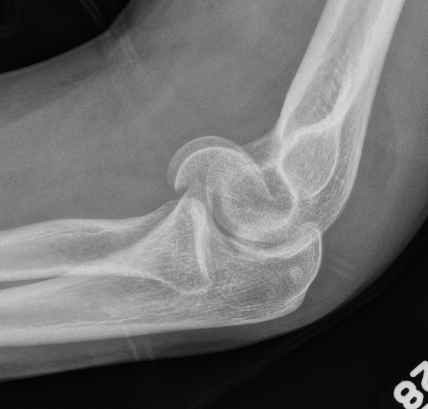

Coronal shear fracture of the distal humerus

Capitellum +/- trochlea

Double arc sign on xray